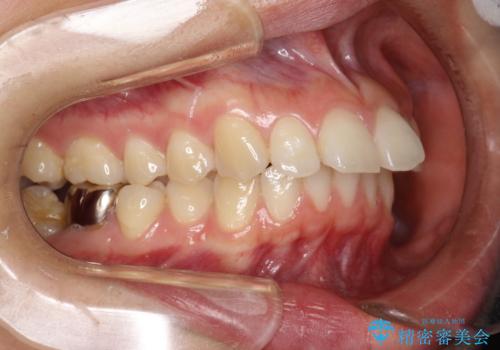

- 矯正装置

- 審美装置

- 治療計画

- 出っ歯を気にして来院されました。

しっかり前歯を下げるために抜歯を合計3本行いワイヤーにて矯正を行う計画としました。